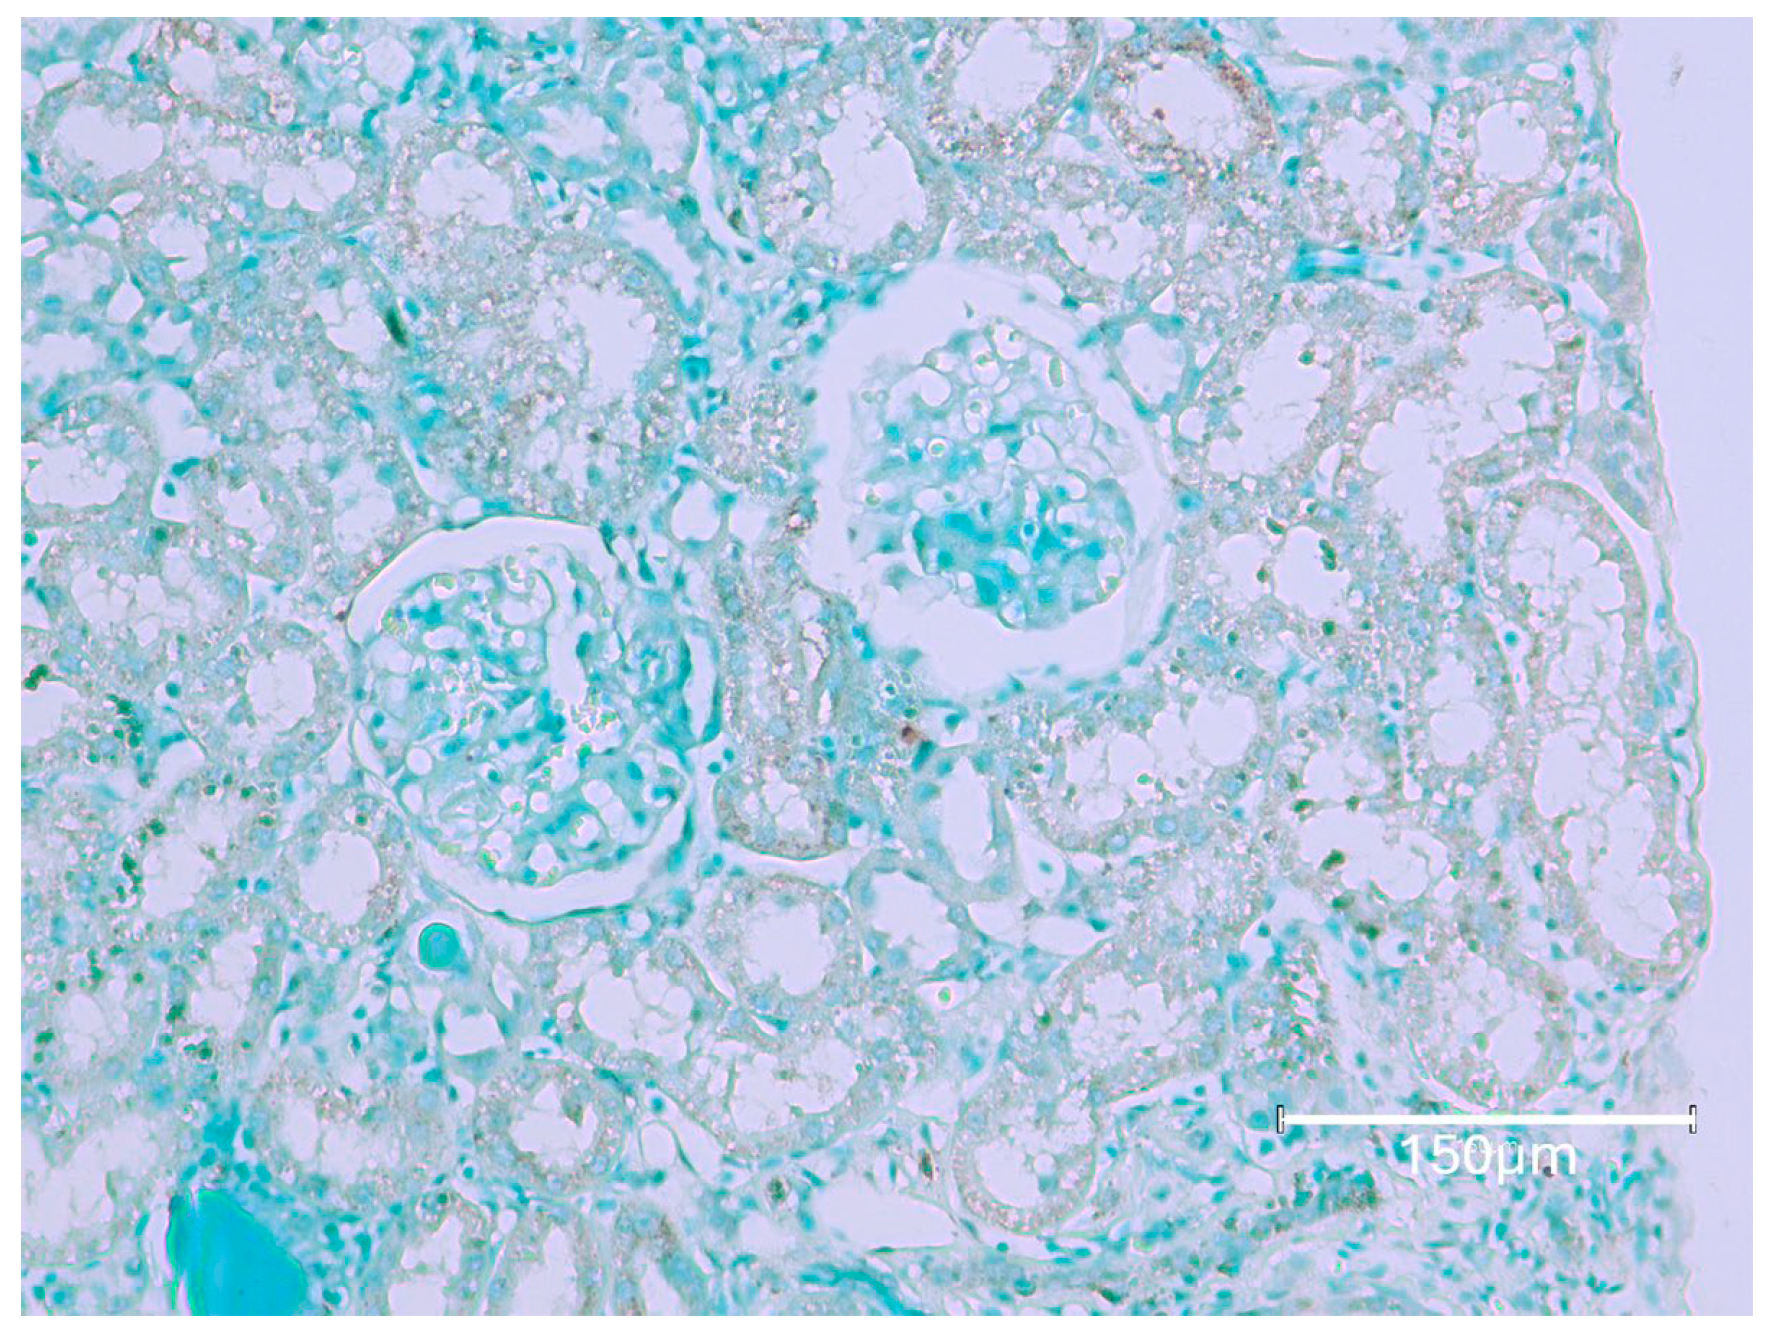

2.1. Carcinogenic Dose of Ochratoxin for Life for Three Fischer Rats

2.2. Low-Dose Ochratoxin for Life for Three Fischer Rats

2.3. Fischer Rat—Second Year OTA Only

2.4. Dark Agouti Rat—SINGLE RAT